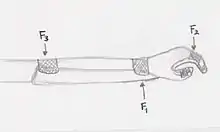

Initial design diagram for a resting orthosis.

Initial design diagram for a resting orthosis. Stabilising Forces F1 wrist flexion force, F2+F3 - forces opposing wrist flexion

Stabilising Forces F1 wrist flexion force, F2+F3 - forces opposing wrist flexion Stabilising Forces F1 - radial deviation force, F2+F3 - forces opposing radial deviation, F4 - ulnar deviation force, F5+F6 - forces opposing ulnar deviation

Stabilising Forces F1 - radial deviation force, F2+F3 - forces opposing radial deviation, F4 - ulnar deviation force, F5+F6 - forces opposing ulnar deviation